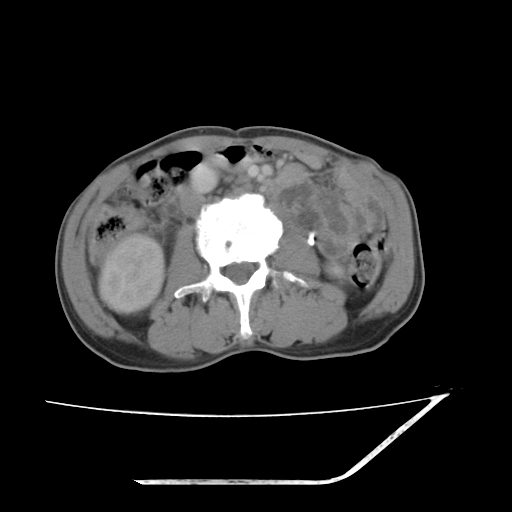

增强

考虑右肾盂癌,肾动脉受侵,右肾功能减退,右肾盂输尿管积水,管壁增厚,考虑种植转移,应该把下面扫完的

支持右侧肾盂癌伴肾静脉瘤栓形成可能性大,右肾结石.肝右叶后段低密度影,不除外转移.

右肾盂旁ca并肾静脉瘤栓形成/肾功能降低。

右肾结石。

右肾盂癌,肾动脉受侵,右肾盂输尿管积水,管壁增厚,考虑种植转移

支持 右侧肾盂癌伴肾静脉瘤栓形成可能性大,右肾结石;肝右叶后段低密度影,不除外转移。

1.右侧肾盂癌伴肾盂积水。

2.肾脏功能减退,原因有:(1)肾动脉受侵。(2)肾静脉受侵(3)肾积水,等。本例,肾动脉显影较好,但受压明显;肾静脉无明显显示,受压或静脉癌栓,下腔静脉腔内未见明显充盈缺损。

3.右侧上段输尿管扩张,原因:(1)积水所致;(2)种植。